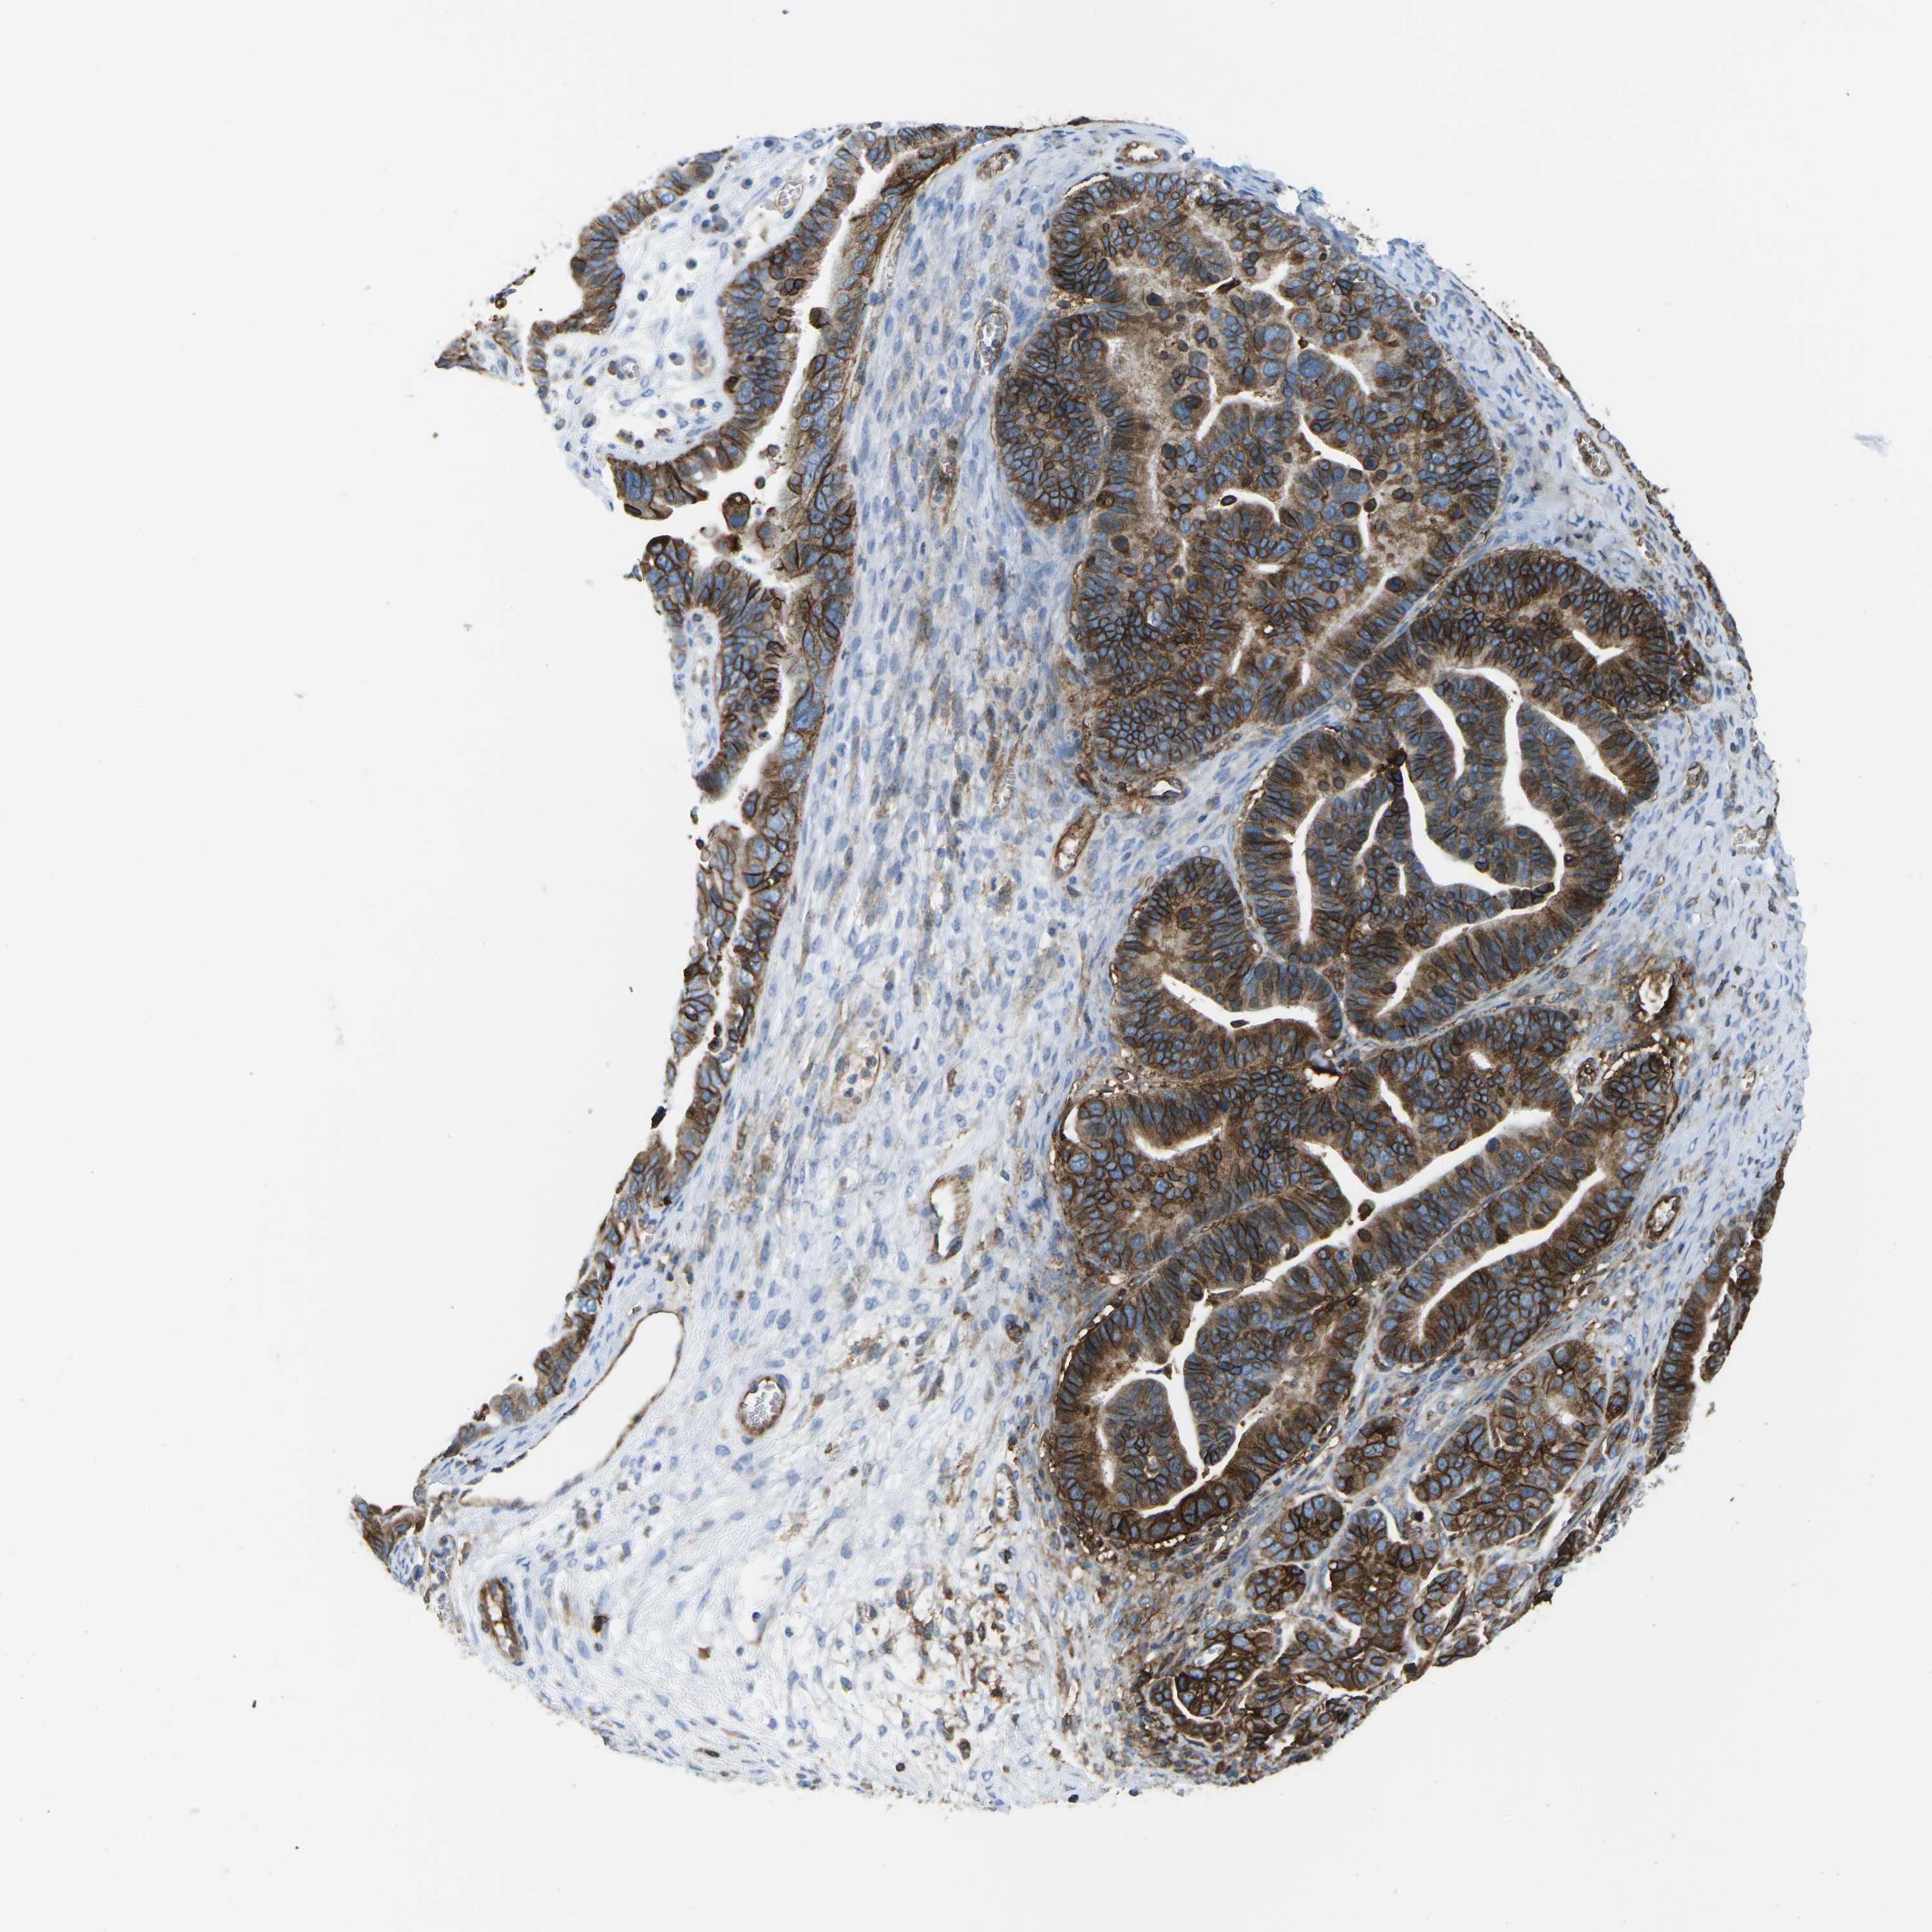

OVARIAN CANCER - Protein expressioni

A mouse-over function shows sample information and annotation data. Click on an image to view it in a full screen mode. Samples can be filtered based on level of antibody staining by selecting one or several of the following categories: high, medium, low and not detected. The assay and annotation is described here.

Note that samples used for immunohistochemistry by the Human Protein Atlas do not correspond to samples in the TCGA dataset.

Antibody stainingi

Antibody staining in the annotated cell types in the current human tissue is reported as not detected, low, medium, or high, based on conventional immunohistochemistry profiling in selected tissues. This score is based on the combination of the staining intensity and fraction of stained cells.

Each image is clickable and will lead to virtual microscopy that enables deeper exploration of all samples and also displays staining intensity scores, fraction scores and subcellular localization as well as patient and tissue information for each sample.

Antibody CAB015418

Staining

High

Medium

Low

Not detected

Intensity

Strong

Moderate

Weak

Negative

Quantity

>75%

75%-25%

<25%

None

Location

Nuclear

Cytoplasmic/membranous

Cytoplasmic/membranous,nuclear

Cystadenocarcinoma, serous, NOS

Carcinoma, endometroid

Cystadenocarcinoma, mucinous, NOS

Carcinoma, NOS